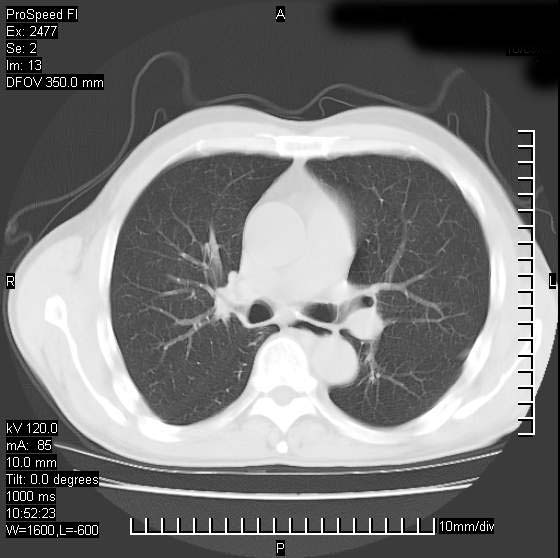

以下是引用天南地北在2007-10-9 14:29:00的发言:[br]1:右上肺结核[br]2:右肺下叶肿块:不支持肺癌,首先考虑炎性病变-肺脓疡可能性大[br]理由:1:临床病史支持,肺脓肿症状不明显应该是不规则服药造成。[br] 2:肿块边缘模糊,周围可见炎性渗出,长毛刺,内见支气管征,不过有点不规则。[br] 我感觉下肺癌这个诊断有点偏左,建议积极抗炎治疗后复查

以下是引用卜一在2007-10-9 15:55:00的发言:[br][br] [br] 1:右上肺结核[br]2:右肺下叶肿块:不支持肺癌,首先考虑炎性病变-肺脓疡可能性大[br]理由:1:临床病史支持,肺脓肿症状不明显应该是不规则服药造成。[br] 2:肿块边缘模糊,周围可见炎性渗出,长毛刺,内见空气支气管征,不过有点不规则。[br] 我感觉下肺癌这个诊断有点偏左,建议积极抗炎治疗后复查![br]支持! [br] [br] [br]

以下是引用wxy7406在2007-10-9 21:02:00的发言:[br]结合临床病史首先考虑感染性病变,但周围型肺癌不能除外,1.患者年龄偏大2.临床有咯血3.(也觉得是最重要的一点)病灶内有偏心性空洞。

以下是引用王仕学在2007-10-9 13:48:00的发言:[br]右下肺周围性肺癌可能性大,最好活检吧

以下是引用hhcckk在2007-10-9 15:18:00的发言:[br]右上肺病灶考虑结核,病灶多种形态并存(纤维化、增殖性病灶并存)[br]右下肺病灶比较难说,个人意见更趋向于“天南地北”的诊断----肺脓肿[br]1、病人有明显的寒战,高热,肿瘤病人很少出现[br]2、病灶周围的肺纹理走向柔和,没有肿瘤病灶常见的集束征[br]3、病灶边缘的毛刺较长,恶性肿瘤多为短毛刺[br]痰中血丝和病人的年龄是两个不利于良性肿块的因素,建议早点活检

以下是引用ydx_74在2007-10-9 15:53:00的发言:[br]右上肺结核,右下中心性肺癌可能大,肺门淋巴结肿大。